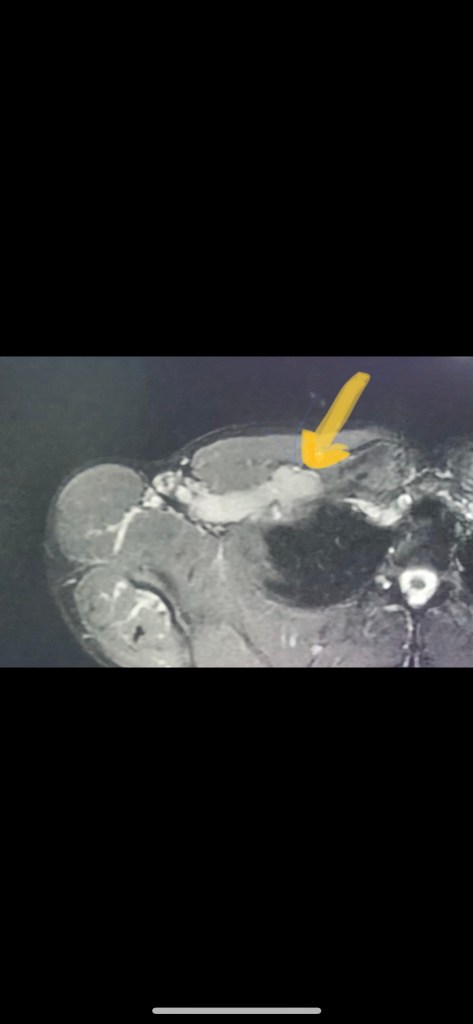

Last November I noticed that the lump in my armpit, which I had previously assumed was a benign lipoma, was not only getting bigger but there appeared to be new ones on top and bottom of it. My worst fear was obviously cancer so I did an ultrasound of it. It was a giant dilated axillary vein with slow flow, which had several focal outpouchings. Still concerned that it could be cancer from a mass blocking the vein in my chest, I did an MRI. The MRI showed subclavian vein compression between my first rib and clavicle, classic Thoracic Outlet Syndrome. Link below for those of you that are unfamiliar with this.

Well I had been noticing more and more shooting pains going down my arm and up my neck well as down my back over the last year but I assumed it had something to do with my offset clavicle and muscle spasms. I had also been getting worse and worse headaches. Not only was there severe narrowing of vein, but there was a giant ballooning aneurysm immediately proximal to it. Pictures below

my armpit/venous aneurysm

Our hospital’s vascular surgeon texted me about a mutual patient right at this time, so I thought, hey what the hell, maybe I’ll ask him if he knows anything about what I should do. I sent him the same MRI clip that I included at the beginning of this post. It was 7 seconds long. He immediately texted me back and said- your SCM muscle, clavicular head, is significantly hypertrophied (basically one of the muscles in my neck was way bigger than it should be) and that’s what’s causing the narrowing. He figured out from just a 7 second clip on his phone something I had spent months trying to do. I had shown that same clip to at least 10 other doctors at this point, in addition to the TOS “expert”, and not one person had figured that out. Once he pointed it out it was like a lightbulb finally turned on in my brain, and everything made sense. It was suddenly so obvious that I felt like an idiot.